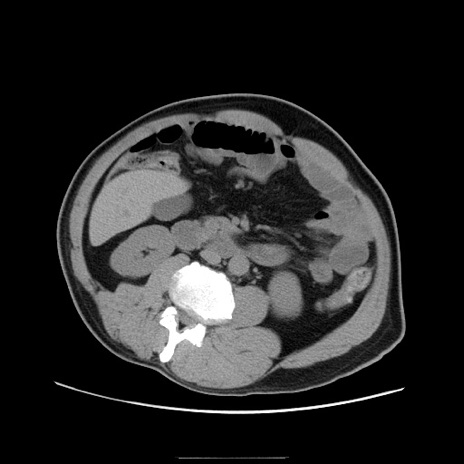

症例22(横断像)

【症例】50歳代男性

【主訴】腹痛

【現病歴】AVMからの被殻出血のため回復期リハ病棟入院中。 本日午後3時頃急に下腹部痛が出現した。

【既往歴】AVM、被殻出血、虫垂炎、高血圧

【身体所見】意識晴明、左半身不全麻痺、会話の理解は良好、36.5°C、腹部:膨隆、全体に板状硬、下腹部正中に圧痛点あり、反跳痛-、筋性防御不明、右下腹部にope scar

【データ】WBC 9400、CRP 0.06